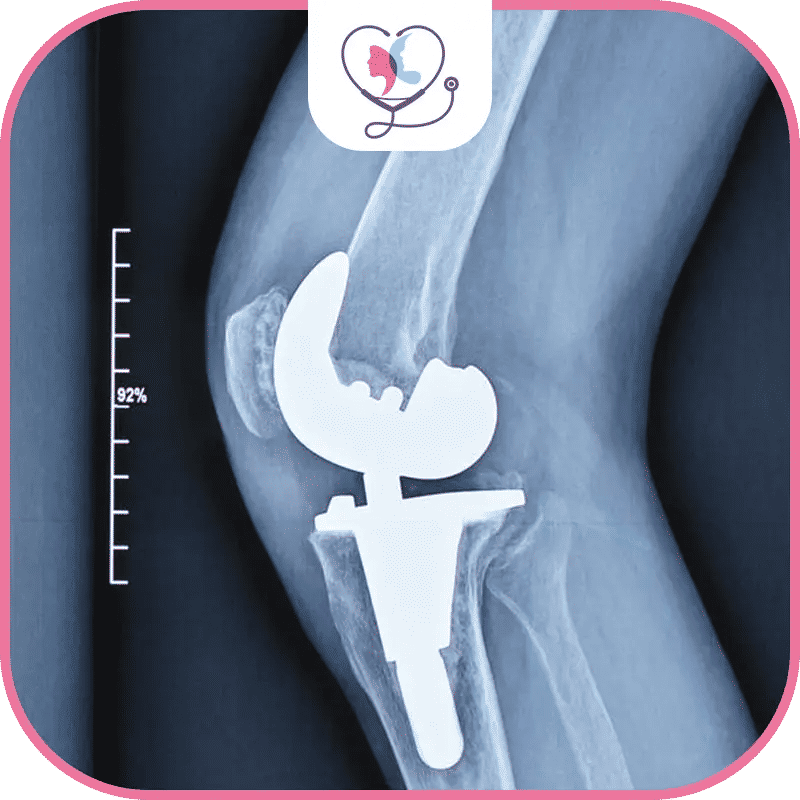

مخاطر عملية تغيير مفصل الركبة

قد تؤدّي عملية تغيير مفصل الركبة إلى زيادة خطورة الإصابة بالنوبة القلبية على المدى القريب! أو خطر تجلطّات الدّم على المدى البعيد؛ نعم .. على الرغم من أنّ نسبة نجاح عملية تغيير مفصل الركبة تتعدى 90% لكن تتعدّد الأضرار الجانبية الناتجة عنها.

مخاطر أثناء عملية تغيير مفصل الركبة

أضرار عملية تغيير مفصل الركبة تتوقّف بشكل كبير على خبرة الطبيب المختص في أغلب الأحيان، ولكن اطمئن إذا كُنت مع أطبّاء تركيا لاكشري كلنيك، لأن أطبائنا مشهودٌ لهم بالخبرة والشهادات السابقة لـ عمليات حقيقيّة وعلى نحو احترافي، أمّا عن المخاطر فهي ما يلي:

- تلف الأعصاب أثناء الجراحة تظهر عبر آلامٍ منتشرة في جميع أجزاء الجسم، أو على شكل وخز وتنميل في الساق، ولكنّها تختفي عادةً بعد حوالي 6 أشهر.

- نزيف غير متوقّع في مفصل الركبة، وعدوى والتهاب مكان الجرح، وبالرّغم من أنّه نادر إلّا أنّه قد يتسبّب بضرر العضلات والعظام وإضعاف المفصل الجديد.

- كسور في عظم الساق أو الفخذ أو الرضفة، وتزداد هذه الاحتمالية إذا كانت خبرة الطبيب ضعيفة، ولذلك نحن خيارك الأفضل .. تواصل معنا فوراً!

مخاطر ما بعد عملية تغيير مفصل الركبة

لا شكّ من أنّك سوف تعاني أضراراً بالغة إذا لم تختر الطبيب المحترف في مجال جراحة العظام، وهذا ما نملكه في جعبتنا بالتأكيد! وتشمل أهم مخاطر ما بعد عملية تغيير مفصل الركبة ما يلي:

مخاطر عملية تغيير مفصل الركبة على المدى البعيد

مع الأسف قد تعاني أضراراً بالغة تستمرّ معك لفترة زمنية طويلة! ولكنّ ذلك نادر الحدوث، دعنا نوضح لك أهّمها فيما يلي:

- آلامٌ مزمنة في الرّكبة بعد حوالي 10 سنوات من تاريخ إجراء العملية.

- تَكوّن عظام جديدة حول العضلات والأوتار والغضاريف والأربطة.

- ارتخاء أجزاء المفصل الصناعي للرّكبة وتآكله مع مرور الوقت مما يستدعي تغييره.